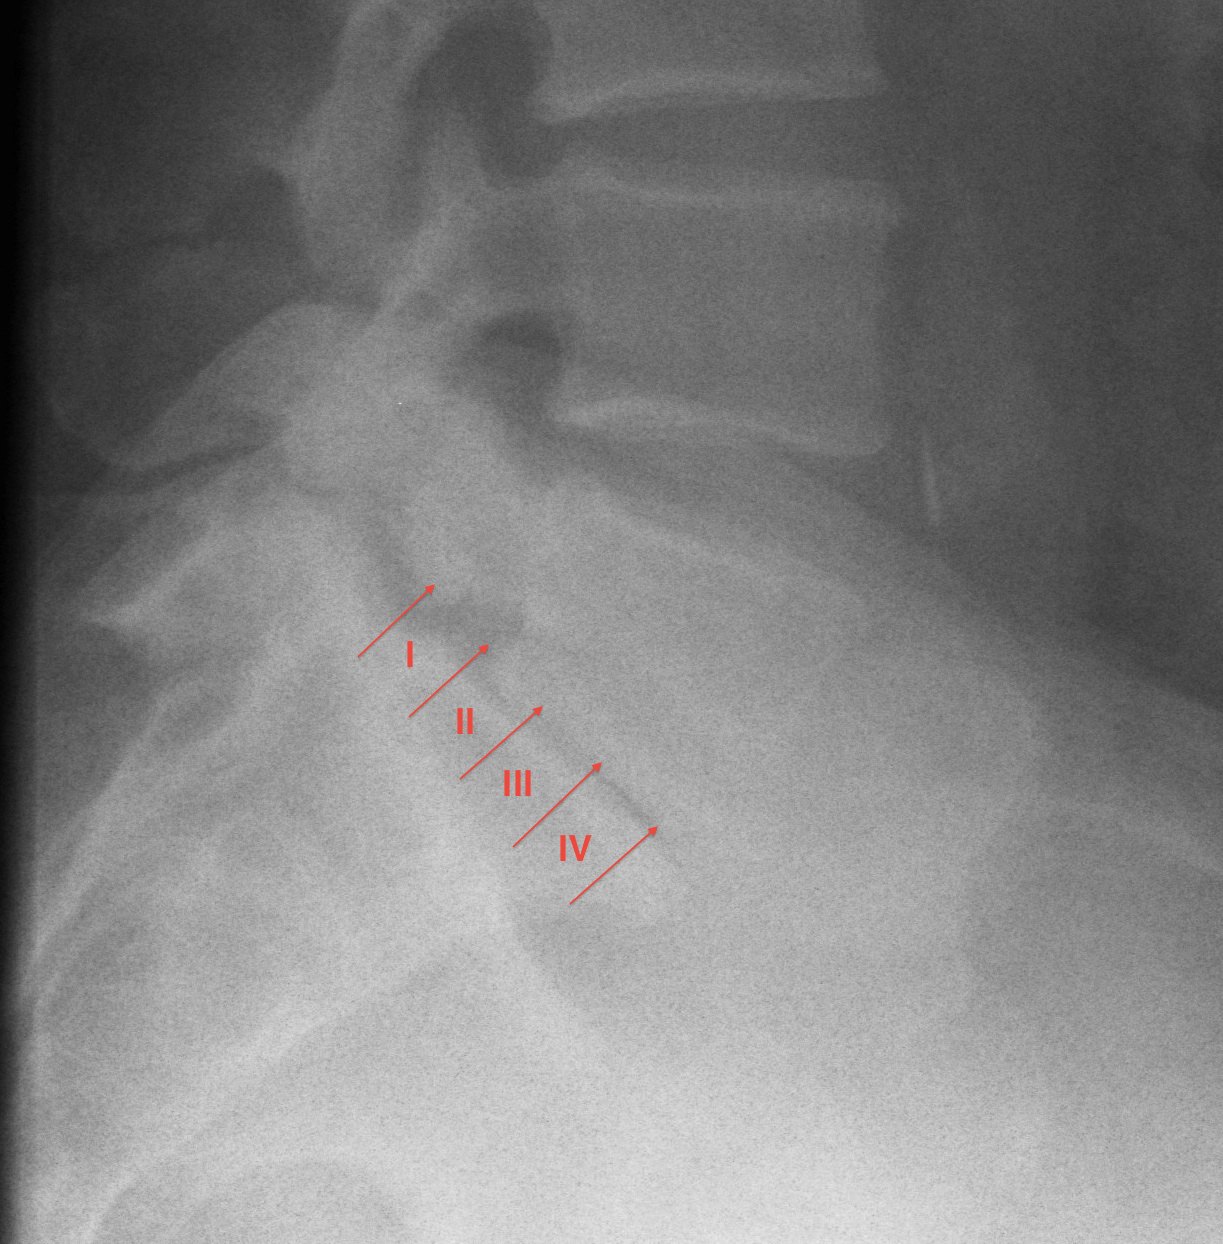

Meyerding Classification

Degree of slip compared with width of S1

- Grade I 0-25%

- Grade II 25-50%

- Grade III 50-75%

- Grade IV 75-100%

- Grade V > 100% / Spondyloptosis

Stability

- stable / slip < 50%

- unstable / slip > 50%